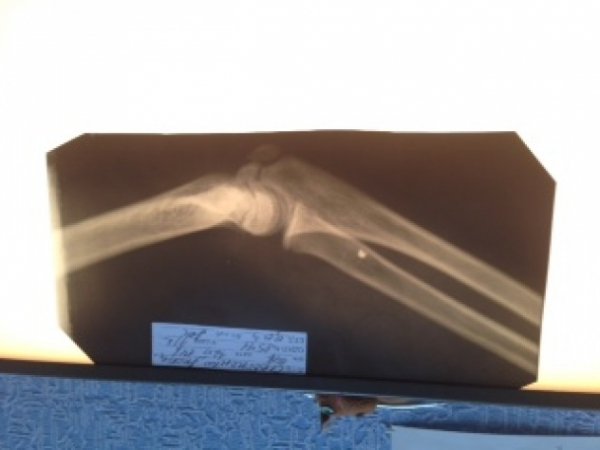

Медикам вдалося врятували лише хлопчика. Його з осколковими пораненнями м'яких тканин грудної клітки, правого плеча та передпліччя доправили до дніпропетровської лікарні.

Під час операції у постраждалого видалили чотири великих осколки і кілька маленьких. Його стан, на щастя, стабілізувався.